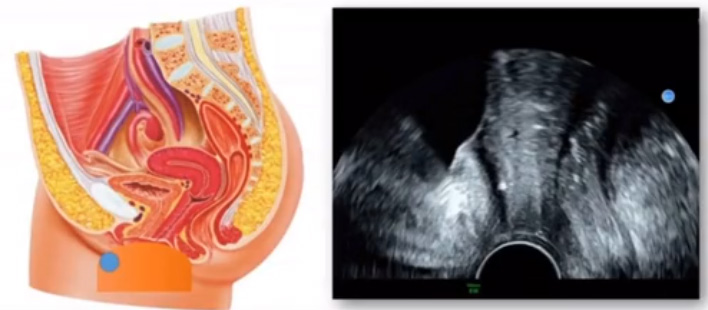

位于輸卵管的后下方,子宮兩側(cè)的后上方;借卵巢系膜與子宮闊韌帶后層相連。正常成人卵巢約4x3x2cm,跟睪丸的數(shù)值差不多,都是性器官,絕經(jīng)后卵巢萎縮變小、變硬。所以絕經(jīng)后婦女很難找到卵巢,主要功能:生殖和內(nèi)分泌功能分泌性激素。女性的第二性征。女性內(nèi)生殖器的血管分布,動(dòng)脈有子宮動(dòng)脈,卵巢動(dòng)脈,陰道動(dòng)脈,陰部?jī)?nèi)動(dòng)脈。靜脈它是與動(dòng)脈伴行。重要了解的是子宮動(dòng)脈,子宮動(dòng)脈是髂內(nèi)動(dòng)脈前干的重要分支,妊娠時(shí)候血流速度會(huì)增加的,為無創(chuàng)性檢查胎盤血管阻力的方法。未孕期頻譜為高阻力低舒張波形;正常妊娠時(shí)血流速度增加,血流阻力下降。